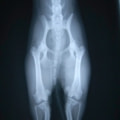

■ 症例24 キャバリア 7か月

左右膝蓋骨内方脱臼(左:グレードⅣ 右:グレードⅢ)

以前から左右後肢の跛行が認められ、整形外科学的検査・レントゲン検査により左右の膝蓋骨脱臼が認められた。症状が重度である左膝の膝蓋骨脱臼整復術を行った。外科手技は縫工筋及び内側広筋の解放、脛骨粗面の外側転位、滑車ブロック形造溝術、内外側関節方の縫縮を実施した。術後一か月時点で、左の膝蓋骨は安定しており経過は良好である。

本症例は成長期における重度の膝蓋骨脱臼であり、術後の再発の可能性もあるため、経過をしっかりと観察していく必要がある。また、今回手術を実施していない右膝に関しても経過を観察し、手術を検討していくこととする。